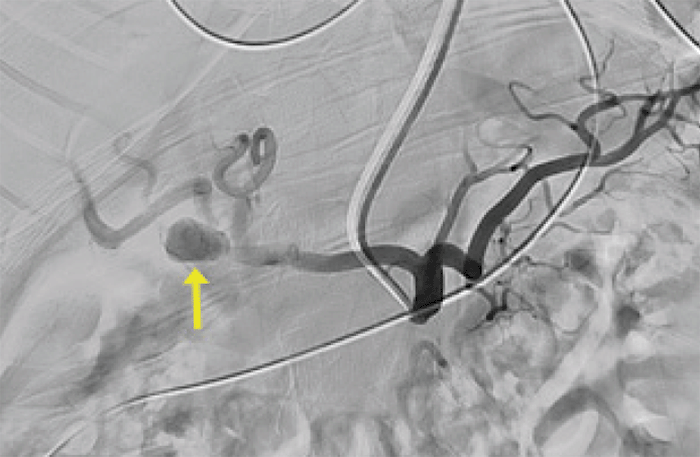

Because of the symptomatic nature of the HAA and the concern for impending rupture, the patient was admitted to the intensive care unit and then taken to the angiography suite, where an endovascular approach was taken, given her hemodynamic stability. Percutaneous access of the left radial artery was obtained, the aneurysm was identified (Figure 5) and coiled utilizing two 20 mm × 50 cm Terumo™ framing coils. Given the diameter of her RHA and the saccular morphology of the aneurysm, coils were utilized to repair the aneurysm. A covered stent was not placed due to concern that it would likely result in thrombosis and obliteration of the arterial lumen.

Figure 5. Angiogram of Right Hepatic Artery Aneurysm. Published with Permission